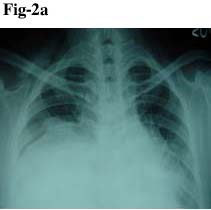

Her past history revealed that in the year 2002, the patient had a thoracotomy for anterior mediastinal mass. The patient was admitted with the same complain and a chest X-ray (Fig. 2a) and subsequent CT scan (Fig. 2b) revealed a large lesion mostly in right hemithorax and partly on the left side with evidence of compression on superior vana cava and pulmonary arteries with their posterior displacement. Significant lung compression was also present at that time. The patient underwent right sided thoracotomy on February 2002. The encapsulated mass was completely excised including the capsule. Histopathology revealed lipoma and no evidence of malignancy. Post operative recovery was uneventful with satisfactory lung expansion. The patient was alright for the last few years but again developed the same complaints of dyspnoea (2009) and was admitted in the hospital once again. As mentioned ealier, X-ray and CT scan revealed a lipomatous lesion which was subsequently cinfirmed by CT guided FNAC. The final radiological diagnosis was recurrence of mediastinal lipoma.

Fig 2b. CT scan of chest shows a large, non-enhancing hypodense mass in the anterior mediastinum.